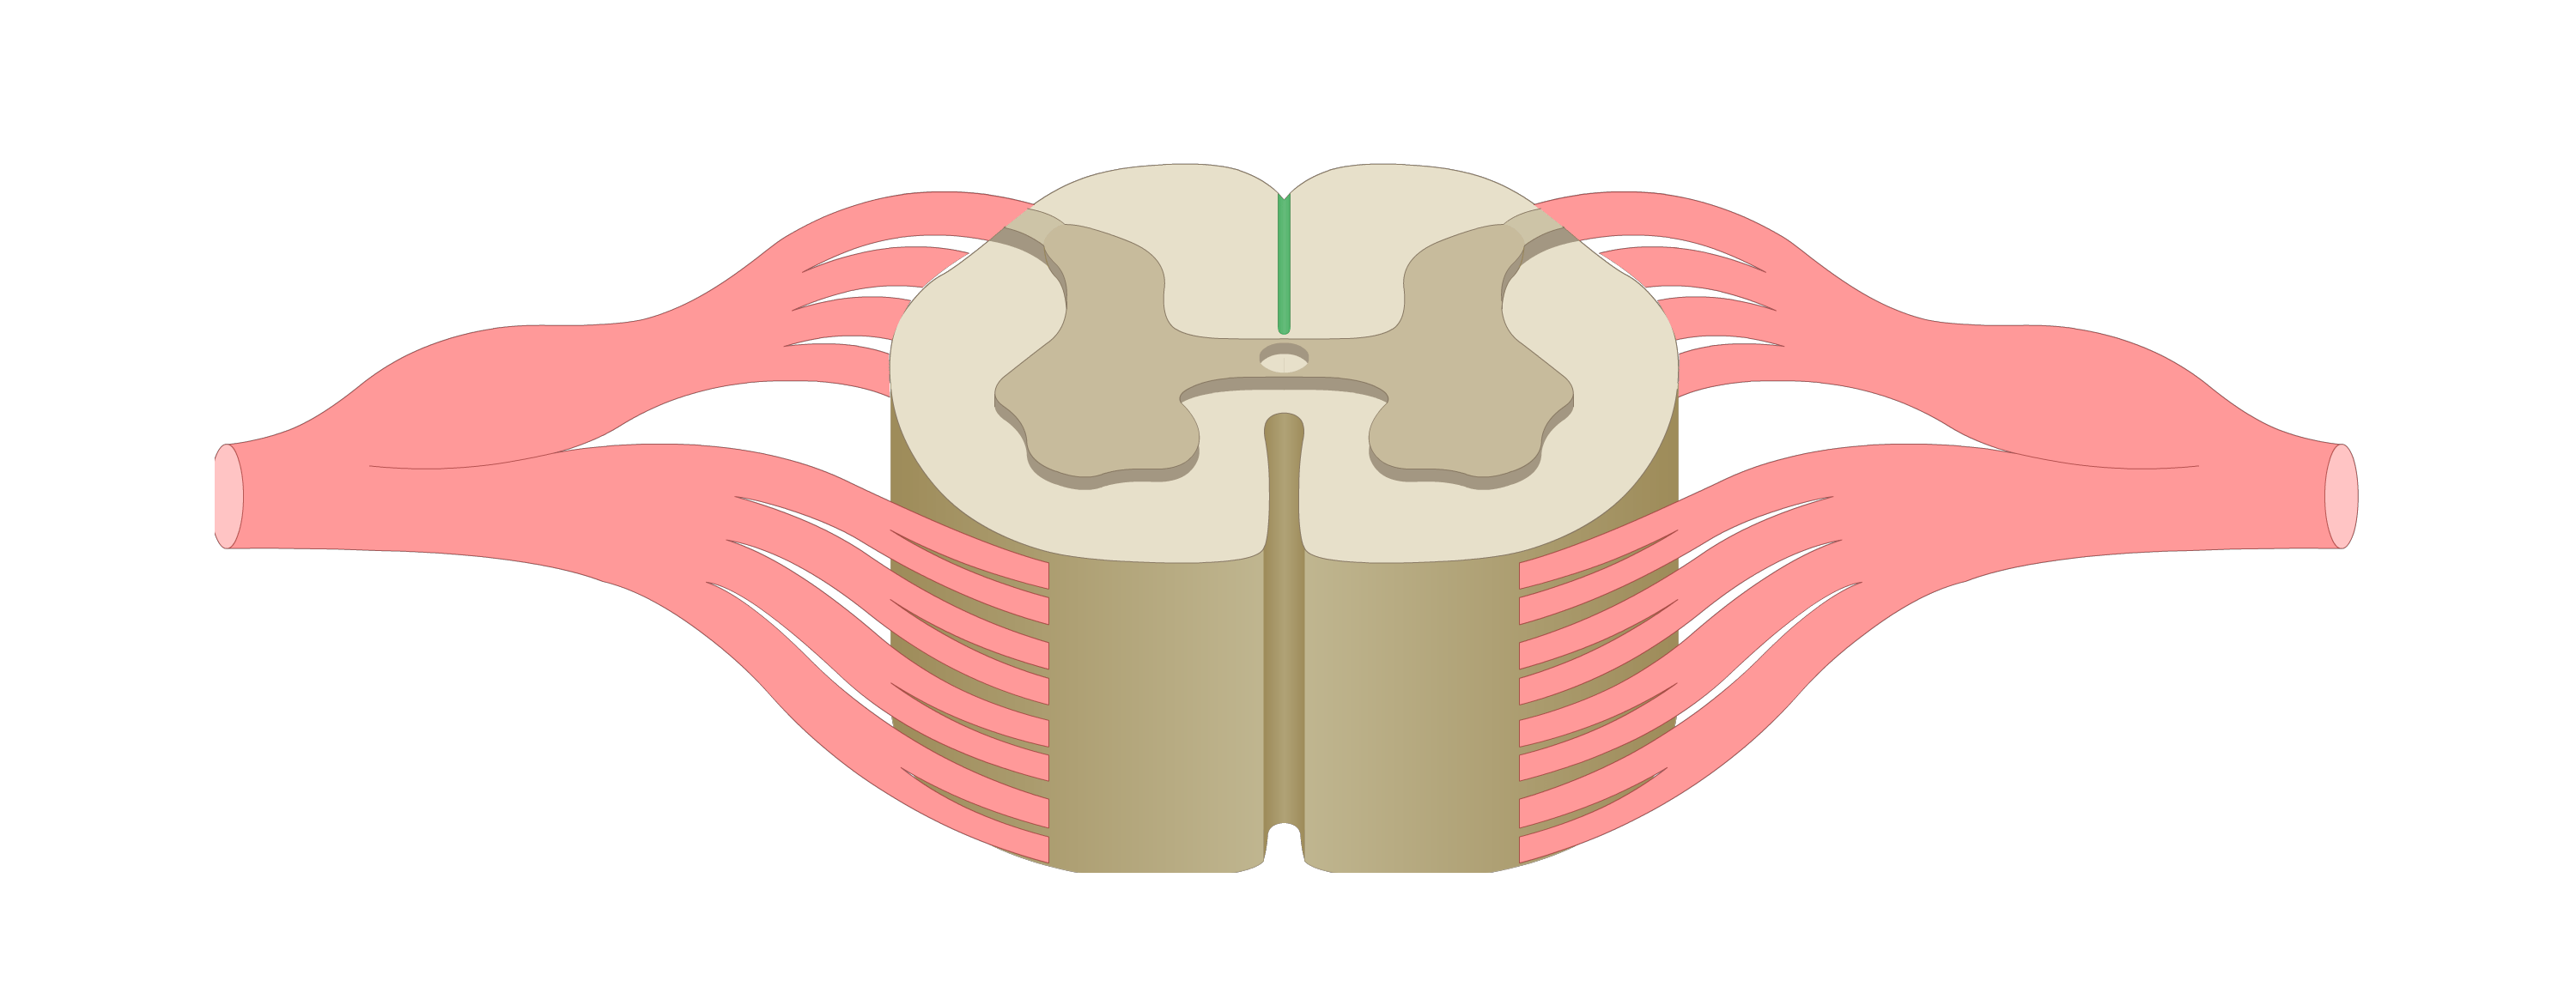

motor tracts

sensory tracts

dorsal root ganglion

dorsal horn

lateral horn

ventral horn

dorsal funiculus

lateral funiculus

ventral funiculus

central canal

ventral median fissure

dorsal median sulcus